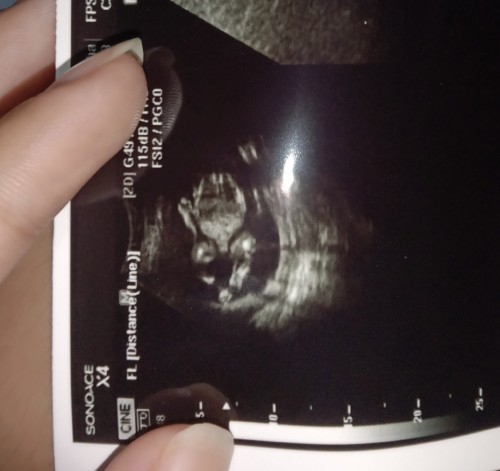

ผู้ชายค่ะ 21w แล้วค่ะตอนนี